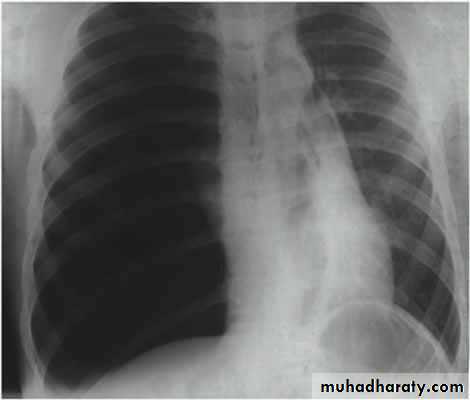

Pneumothorax

!! pneumothorax

(Collapse) (Massive plural effusion)